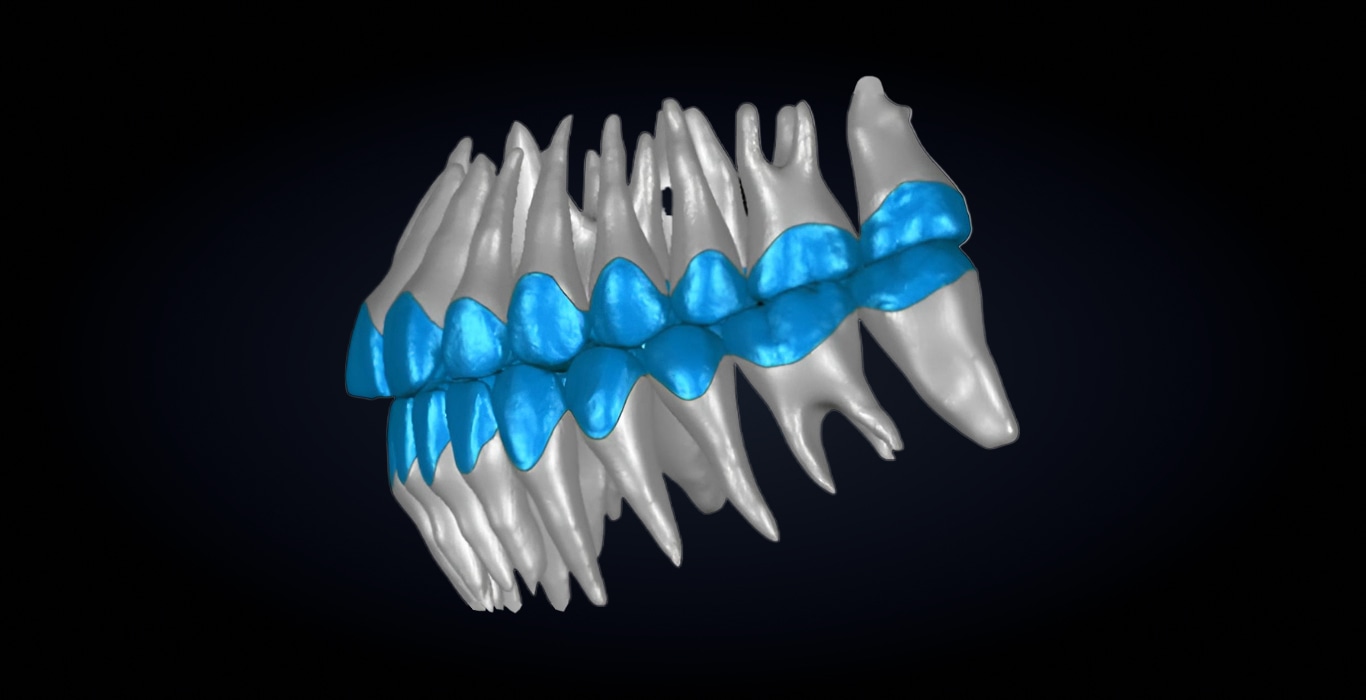

Основана на AI-платформе masterEngine¹¹ и данных КЛКТ (конусно-лучевой компьютерной томографии). Объединяет 3D-модель корней и челюсти с внутриротовым сканом, создавая точное цифровое отображение анатомии пациента в масштабе 1:1.

В отличие от имитационных моделей, IRS10 предоставляет врачам реальные данные о форме и положении корней, что позволяет анализировать и корректировать их расположение прямо в интерфейсе iOrtho⁸. Система обеспечивает точную визуализацию, анализ и редактирование корней, помогая врачу точно контролировать тип движения зуба и добиваться стабильных и предсказуемых клинических результатов.